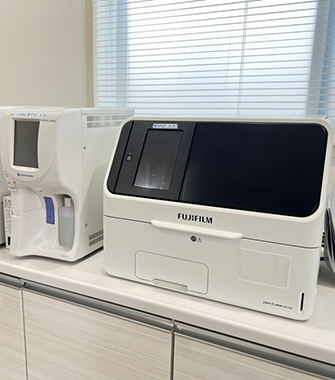

当院ではAI技術を活用した胸部X線画像病変検出ソフトウェアを導入しております。

解析結果画像を自動的に作成することにより、医師の画像診断支援、病変の見落とし防止、患者様への分かりやすい画像説明に役立てています。

C@RNACORE・「CXR-AID」